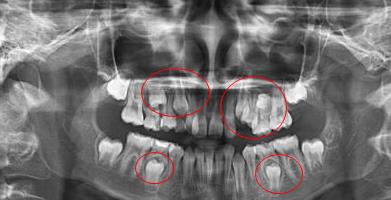

全景片,簡單的說,就是可以把口腔內(nei) 的全部情況展現出來的片子,包括全部的牙齒以及牙根、牙槽骨等等,可以在醫生指導下,一目了然的看清自己的牙齒情況,那麽(me) 這種片子到醫院拍要多少錢呢? 深圳牙科醫院醫生表示,不一定。...

全景片常用於(yu) 正畸,主要是為(wei) 了了解全口牙齒不齊情況,方便製定牙齒矯治方案;

此外,在智齒拔牙也要使用,可以很清晰的查看智齒的位置,牙根情況,以及和下頜神經的距離等,方便醫生確定拔牙難度。

再有,種植牙之前也是需要的,查看口腔牙齒缺失位置牙槽骨情況以及鄰牙情況,以及是否有殘根、多生牙等等,這樣方便做好種植牙術前準備和製定合適的修複方案,不僅(jin) 如此,種植牙還需要做口腔CT片查看更多的信息。